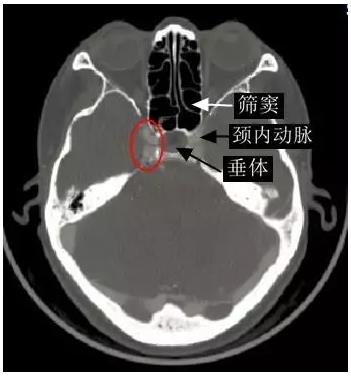

海綿竇位置影像顯示 (橫斷面),增強磁共振圖像(下圖中紅圈內高信號區即右側海綿竇)

腫瘤累及左側鞍旁、左側海綿竇、篩竇及左側眼眶。